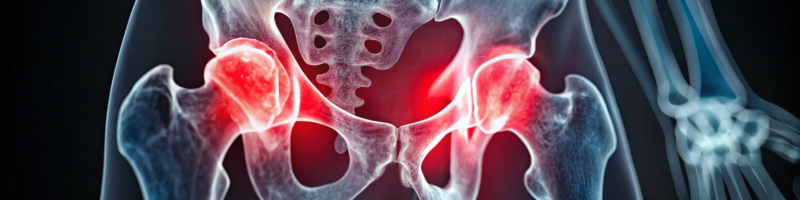

A osteoporose é uma condição em que ocorre diminuição da massa óssea e deterioração da estrutura dos ossos. Isso faz com que eles percam resistência, aumentando significativamente o risco de fraturas, principalmente na coluna, no quadril e nos punhos.

Com o avanço da doença, podem surgir sinais indiretos, como diminuição da altura, postura curvada e dores nas costas, geralmente associadas a fraturas vertebrais. Por isso, exames preventivos são fundamentais, especialmente em pessoas com fatores de risco.